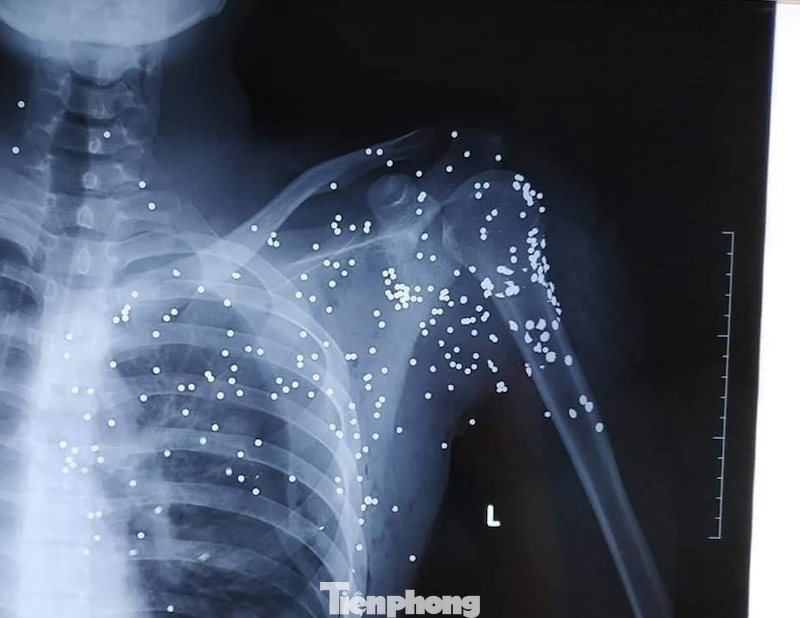

Hứng trọn cả viên đạn hoa cải vào người, anh H. gục xuống. Nạn nhân sau đó được người dân hô đưa đi cấp cứu tại bệnh viện Đa khoa tỉnh Thái Bình trong tình trạng đa chấn thương. Vị trí bị bắn tập trung ở vùng cổ, vai trái và phía trên ngực trái, mất nhiều máu.

Xác nhận nạn nhân bị các mảnh đạn hoa cải găm dày đặc ở vùng phổi, tình trạng nguy kịch, các bác sỹ đã nhanh chóng phối hợp cùng gia đình chuyển anh H. lên cấp cứu tại bệnh viện Hữu nghị Việt Đức.

Theo anh trai của B.H.H, suốt đêm qua nạn nhân được các y bác sỹ tiến hành cấp cứu, gắp các mảnh đạn trên người.

Tuy nhiên, đến sáng nay, anh H. vẫn chưa qua cơn nguy kịch. Trên người nạn nhân vẫn còn một số mảnh đạn đang được xử lý, trong đó đặc biệt nguy hiểm là có một số mảnh đạn găm vào khu vực tim nạn nhân.

Phim chụp cho thấy trên ngực nạn nhân chi chít các mảnh đạn hoa cải - Ảnh: BXH